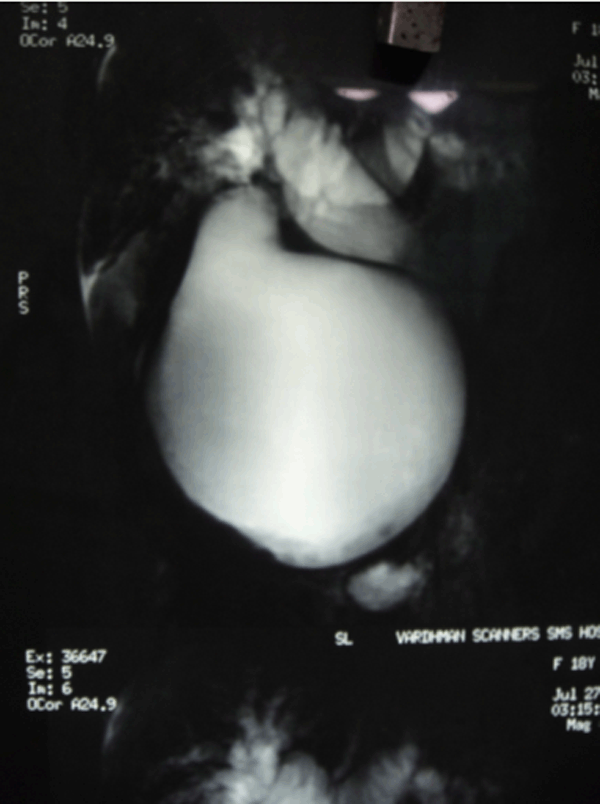

On further investigating the patient, magnetic resonance cholangiopancreatography (MRCP) showed a large cystic dilatation of CBD measutring 11.8x11.6x11.6 cm (type-I choledochal cyst) with minimum sludge in dependent position likely to be choledochal cyst. Also seen were dilated IHBR and hepatic ducts, nodular liver, splenomegaly, displaced portal vein with recanalization of left umbilical vein and ascites (Figure 1). An upper gastrointestinal endoscopy revealed grade 1 esophageal varices with proximal gastropathy. Serum-ascites albumin gradient (SAAG) was >1.1 g/dL wich was suggestive of portal hypertension.

Cursor on image to zoom/Click text to open image

Figure 1: Magnetic resonance cholangiopancreatography (MRCP) suggestive of choledochal cyst and dilated intra-hepatic biliary radicle.